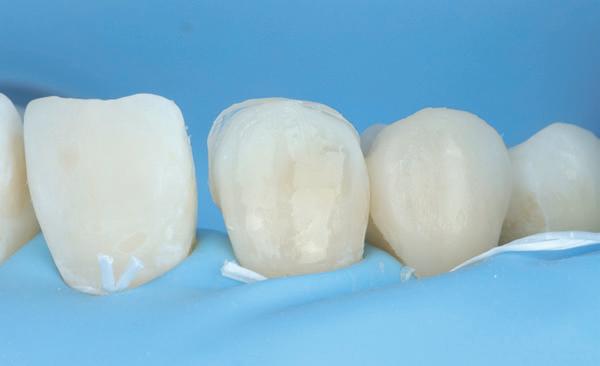

Voordat er gescand kon worden voor een etsbrug, werd een studiemodel vervaardigd om met de technicus te overleggen of er voldoende ruimte was voor 2 centrale incisieven in de mesio-distale zin en of er voldoende ruimte was in occlusie voor de vleugels van de etsbrug. Er hoeft enkel nog aan de 12 en 22 pala-

tinaal geslepen te worden als er geen 1,5 mm ruimte voor de vleugels behaald kan worden. De ruimte was op de dunste plekken 1 mm, dus een kleine preparatie in de 12 en 22 palatinaal was nodig. Omdat de kaak volledig afgevlakt was en dun was geworden, kunnen de dummies van de etsbrug enkel op de kaak “gelegd worden”, maar daarbij zijn er geen papillen en staat de cervicale rand van de dummies net voor de kaak. Een esthetisch resultaat kan daarmee niet behaald worden. Daarom is een aanvulling van de zachte weefsels in de breedte nodig, als het creëren van een emergence profile, waarbij het oogst alsof de gebitselementen uit het weefsel vertrekken.

18. Etsbrug frontbeeld

19. Etsbrug palatinaal